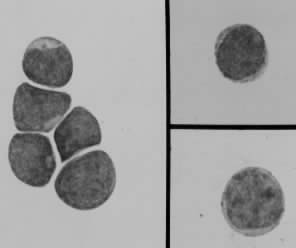

图为造血干细胞